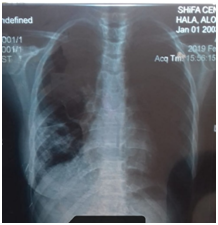

Female Patient (PT) 15 years old, referred to our hospital after more than 6 months of recurrent infections in right lower lobe (RLL) of the lung Figure A1 & A2. The PT had investigated, CXR was done Figure A3. The sputum was negative for TB many times. Bronchoscopy was done, no foreign body, no tumor, no anomalies, the washing was tested for TB and was negative. The decision for surgery was taken, the RLL was contracted, nodular and solid. RL Lobectomy was done. At second day post operation the PT had fever, sweat, no appetite and bad general condition. CXR revealed bilateral diffuse infiltrations. Figure B1. We decided to give her a trial TB treatment. After five days PT began to respond clinically. So TB treatment for minimum 6months is ordered.

B1 26-6-2019